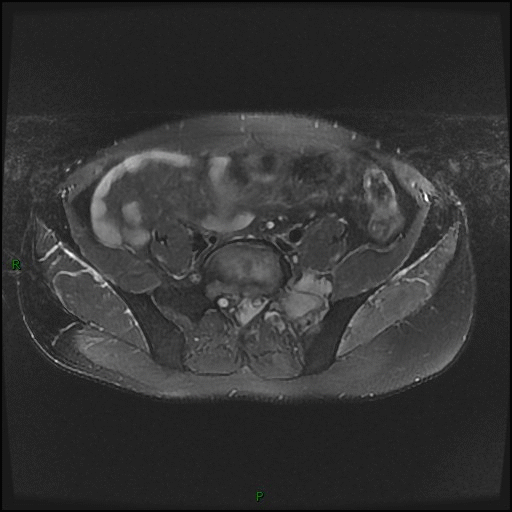

MR 平扫及增强

依据:病灶大,骨质破坏同时突破骨皮质于骨旁形成软组织肿块,骶骨形态存在。病灶骨质破坏相对较轻,而软组织肿块明显。MR 平扫病灶信号均匀,未见明显坏死成分。增强后病灶明显均匀强化。病灶周围可见肿大淋巴结,增强后肿大淋巴结明显均匀强化。

PBL 的 MR 表现:病灶以 T1WI 低或等信号、T2WI 等信号为主,偶呈高信号(细胞排列紧密,水分少),T2WI 压脂呈高信号。淋巴瘤常形成体积较大的软组织肿块,位于椎体者常包绕椎体,并常常累及椎管,因硬膜具有一定阻挡作用,故肿块多位于椎管内硬膜外,可包绕椎管四周生长,形成「袖套」或「肉包骨」样改变。增强肿块一般轻中度均匀强化,坏死囊变少见。